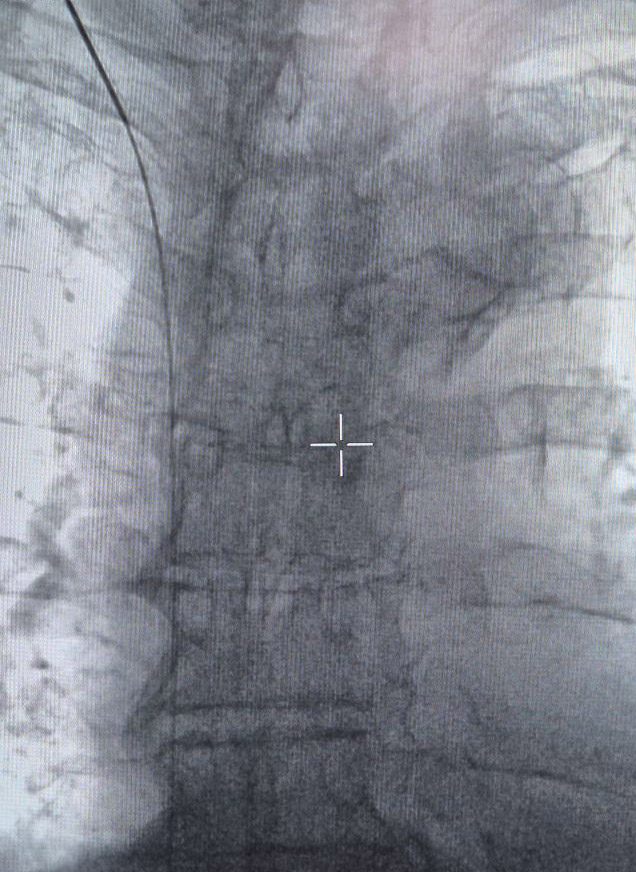

Εισάγεται καθετήρας στη μηριαία αρτηρία ή φλέβα και χορηγείται σκιαγραφικό υλικό για να εντοπιστεί η περιοχή του προβλήματος, μέσω του καθετήρα εισάγονται υλικά για την απόφραξη του αγγείου.

Επαληθεύεται η επιτυχία με νέες αγγειογραφικές εικόνες, τότε ο καθετήρας αφαιρείται, και η θέση του κλείνεται.

Η διαδικασία εμβολισμού χρησιμοποιείται για τη θεραπεία ανωμαλιών των αιμοφόρων αγγείων